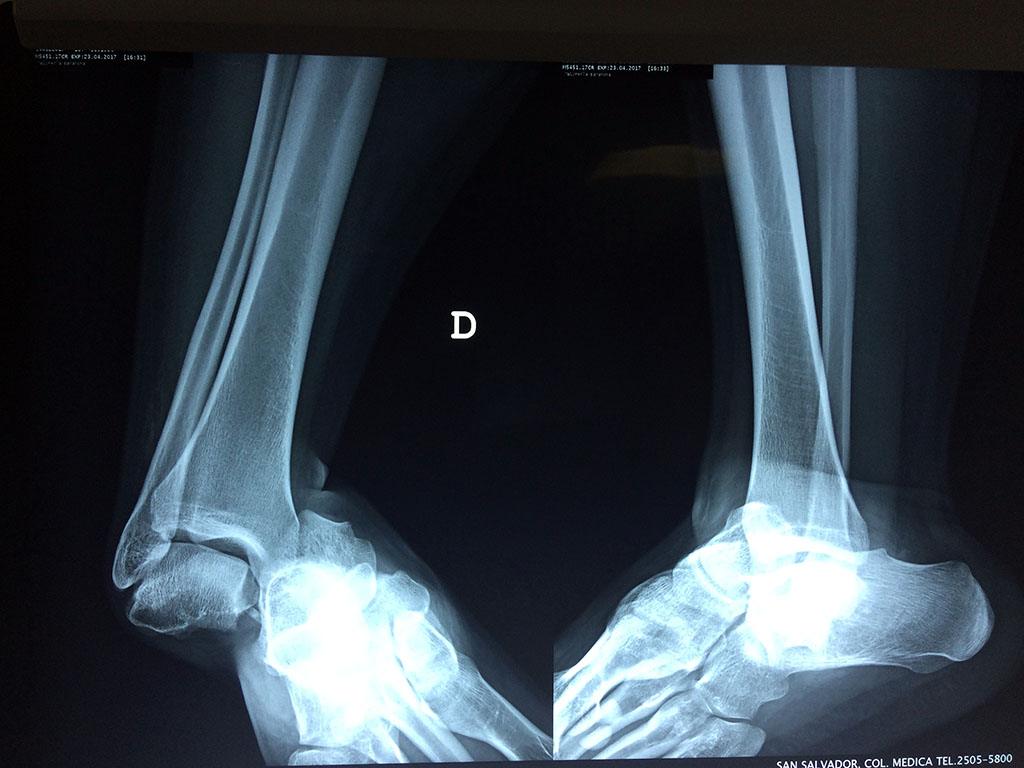

Una fractura de tobillo es la rotura de uno o más de los huesos del tobillo. Estas fracturas pueden ser:

- Parciales (el hueso está sólo parcialmente fisurado, no del todo).

- Completas (el hueso está perforado y está en 2 partes).

- Producirse en uno o ambos lados del tobillo.

- Los extremos de los huesos están desalineados entre sí (desplazados).

- La fractura se extiende hasta la articulación del tobillo (fractura intra-articular).